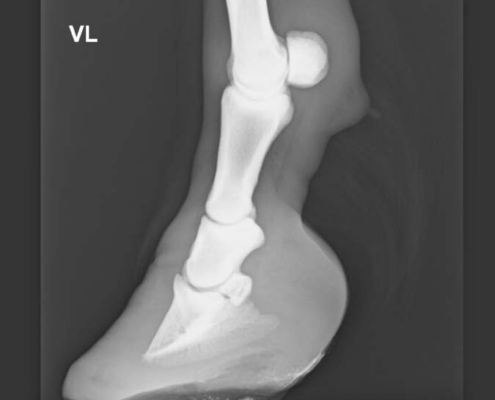

Hufeisen für Rehhufbeschlag

Bei dieser Krankheit, welche vorwiegend an den Vorderhufen, selten auch an den Hinterhufen auftreten kann, ist es wichtig, dass das Pferd möglichst schnell vom Tierarzt behandelt wird. Hier ist es wichtig, dass Tierarzt und Hufschmied zusammen den für das Pferd geeigneten Beschlag definieren. Heute wird anhand von Röntgenbildern entschieden, wie der Beschlag auszusehen hat. Dieser Entscheid hängt von der Rotation oder Absenkung des Hufbeins ab. Ein frühes Erkennen dieser Krankheit ist entscheidend. Zunehmend wird heute geklebt, um das gehen der Pferde zu unterstützen.